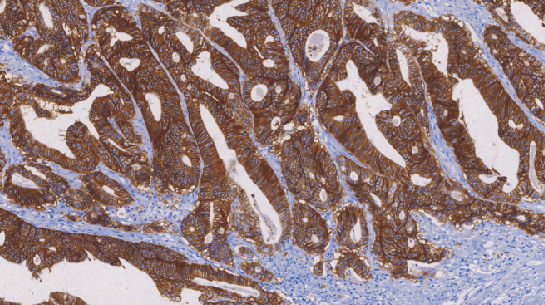

上皮抗原在上皮细胞中广泛分布,在上皮来源的肿瘤中具有高度保守性表达的特性。腺癌细胞阳性反应表现为弥散的胞质、胞膜着色;而间皮瘤则是少量细胞弱的局灶性胞质着色或阴性表达。

- 阳性部位:胞膜

- 适用组织:石蜡切片

- 预处理:热修复